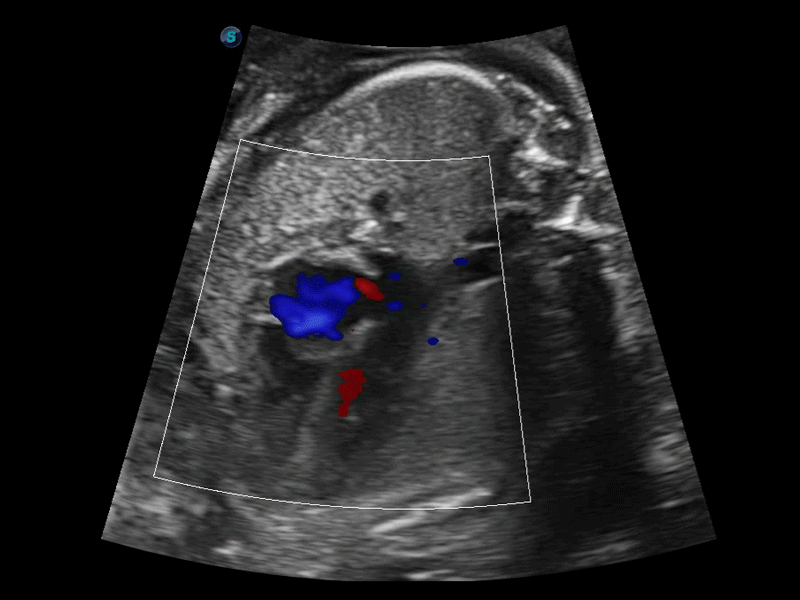

開(kāi)立醫(yī)療通過(guò)不斷的技術(shù)創(chuàng)新,為大眾的生命健康提供持續(xù)關(guān)愛(ài)。P12 Plus采用全新一代超聲成像平臺(tái),新平臺(tái)旨在將真實(shí)還原組織解剖結(jié)構(gòu)作為首要目標(biāo)。平臺(tái)采用全新集成化硬件模塊,搭載新一代芯片,系統(tǒng)性能得到大幅提升,為您的診斷提供了豐富的臨床信息。優(yōu)異的圖像表現(xiàn),豐富的探頭配置,全面的應(yīng)用功能,為您日常診斷提供了可靠的助手。

彩色多普勒超聲診斷系統(tǒng)